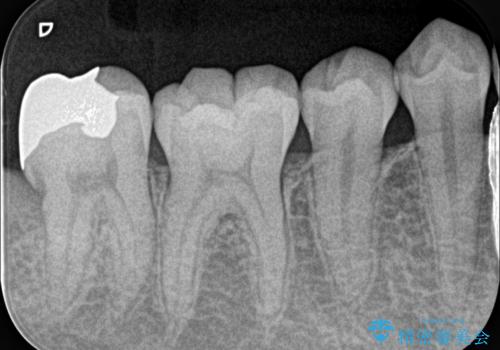

- 親知らずが痛くて抜いて欲しいとの事で来院。CTで神経の位置を確認し、抜歯を行いました。

抜歯後、奥歯にも虫歯があったので虫歯を拡大鏡下で取りきり、メタルインレーにて治療を行いました。